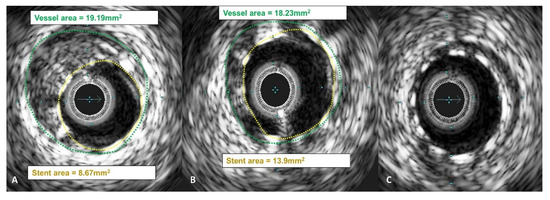

Operators aimed to achieve an optimal anatomical outcome during PCI, guided by IVUS assessment using the following criteria: (1) ensuring proper stent apposition, (2) achieving adequate stent expansion (with a minimal stent area (MSA) greater than 90% of the distal reference lumen area and/or MSA of at least 5.5 mm2), (3) maintaining a plaque burden below 50% within 5 mm proximally and distally to the stent, and (4) avoiding stent edge dissection. A case example demonstrating stent expansion and apposition is demonstrated in Figure 3 and Figure 4.

Figure 4. IVUS images demonstrating stent malapposition. In picture (A), malapposed stent struts are visible on one side of the artery. In picture (B), the malapposed stent struts are marked with a yellow line, and the red lines indicate the distance between the stent struts and the vessel wall inner layer.